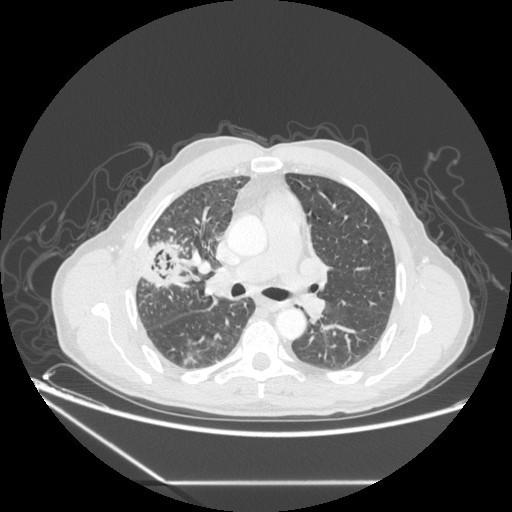

A 60 year old male with a long standing history of smoking was referred to our department for surgery of aspergilloma in right upper lung lobe diagnosed by computed tomography and confirmed by computed tomography guided needle aspiration biopsy. A lobectomy was performed. Histological study of the surgical specimen revealed a pulmonary adenocarcinoma associated with aspergilloma. By presenting this case we suggest that every case of pulmonary aspergilloma should be examined for malignancies, especially in smokers.

一位 60 岁男性,长期吸烟史,因 CT 诊断的右上肺曲霉球,并经 CT 引导下针吸活检证实,转入我科行手术治疗。行肺叶切除术。手术标本的组织学研究显示与曲霉球相关的肺腺癌。通过本例报告,我们建议对每个曲霉球病例都应检查恶性肿瘤,特别是在吸烟者中。